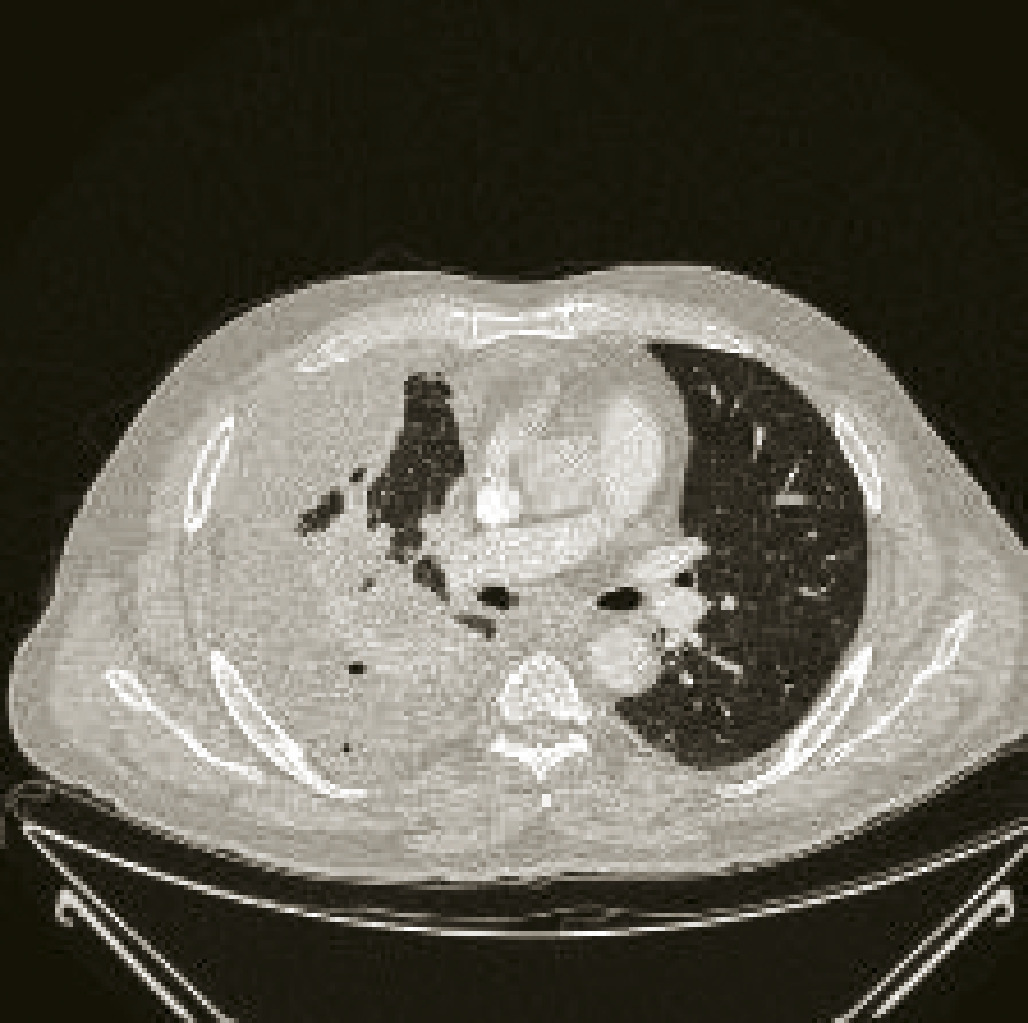

Voici ci-contre, afin d’illustrer l’importance à accorder à la recherche et la découverte de mutations d’intérêt thérapeutique, le cas d’un homme de 51 ans, non-fumeur, chez qui l’on découvre un adénocarcinome bronchique stade IV avec envahissement pleural et ganglionnaire majeur. Lafigure 1 correspond à son imagerie thoracique avant traitement, la figure 2 à son imagerie de réévaluation après traitement par un TKI de première génération ciblant sa mutation activatrice de l’EGFR.•

Voici ci-contre, afin d’illustrer l’importance à accorder à la recherche et la découverte de mutations d’intérêt thérapeutique, le cas d’un homme de 51 ans, non-fumeur, chez qui l’on découvre un adénocarcinome bronchique stade IV avec envahissement pleural et ganglionnaire majeur. La